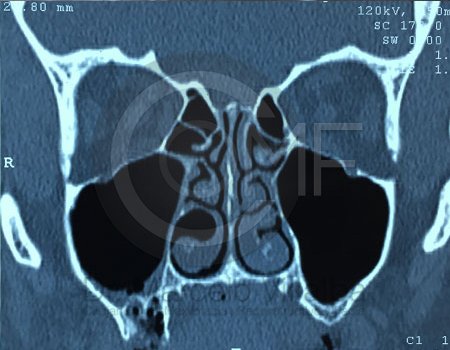

Antes de la extracción se realiza una valoración clínica y estudios de imagen, como radiografías panorámicas o tomografías, para conocer la posición del tercer molar, su relación con los nervios y planificar un procedimiento seguro y adecuado para cada paciente.

Es una conexión entre la cavidad oral y el seno maxilar que puede ocurrir tras extracciones o infecciones. Su tratamiento busca cerrar adecuadamente la comunicación para evitar molestias e infecciones sinusales.